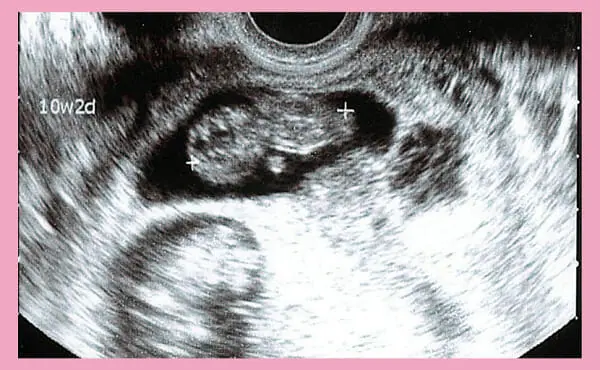

Ultrasound photo from the 10th week of pregnancy.

An ultrasound examination at around 10 weeks of pregnancy will allow you to see the baby’s movements.

Until then, you could only see the sound of your heart beating rapidly during an ultrasound examination, but at 10 weeks of pregnancy you can hear the thumping heartbeat quite clearly.